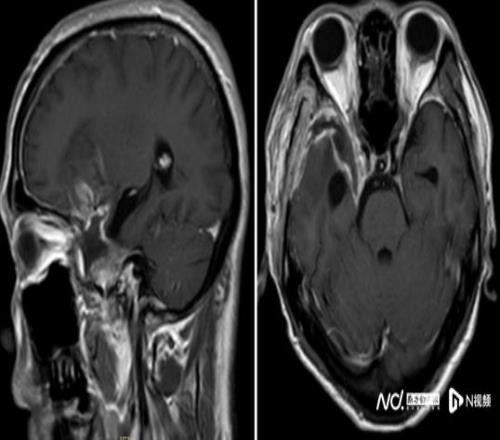

鉴于肿瘤体积巨大、位置较深,考虑为右侧额颞蝶骨嵴内侧型巨大脑膜瘤,肿瘤突入垂体窝和斜坡,环绕颈内动脉及分支、视神经等重要结构,压迫脑干。手术难度是神经外科最复杂的手术之一,犹如刀尖上行走,且已出现进行性神经功能缺损症状:肢体乏力,视力受损,视物重影等,病情复杂、手术风险极高。

经过近8个小时的精细操作,肿瘤被完整切除,重要神经血管结构完好保留。术后患者恢复良好,顺利出院,经过积极康复后,陈叔有望重回马拉松赛场。